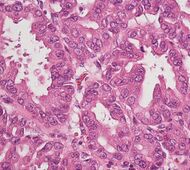

| نوع السرطان | الحدوث النسبي[11] | نتائج الفحص المجهري[11] | صورة مجهرية | علامات كيمياء الأنسجة المناعية [11] | التعديلات الجينية[11] |

|---|---|---|---|---|---|

| السرطانة الغدية القنوية الپنكرياسية (PDAC) | 90% | الغدد والتنسج الليفي | |||